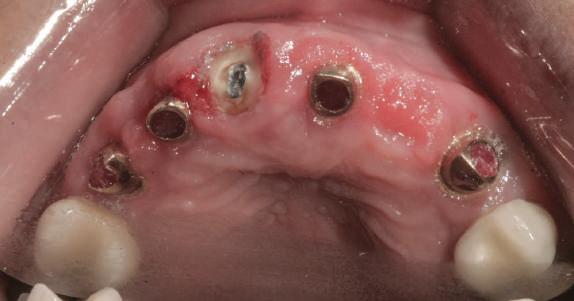

Cazul (4)

Bonturi provizorii

Acest pacient s-a prezentat cu dentiţia mandibulară laterală dreaptă eşuată din cauza unei fracturi radiculare verticale şi a cariei secundare. Autorii au utilizat cilindri de bonturi provizorii, cu şurub, ca metodă iniţială de retenţie pentru puntea provizorie după prima etapă de tratament, care a inclus extracţii şi inserarea de implanturi. Atitudine: Cilindrii temporari înşurubaţi pe implanturi după inserare sunt prezentaţi în fig 13. Ei au fost cimentaţi la carcasa acrilică prefabricată construită pe baza wax-up-ului diagnostic al pacientului (fig. 14). După îndepărtarea acrilatului excesiv, s-a

inserat proteza provizorie fixată cu şurub (fig. 15).

Cazul (5)

Bonturi conice utilizate ca bonturi temporare

Pacienta prezenta boală parodontală generalizată, cu leziuni endodontice secundare. A refuzat ferm proteze mobilizabile provizorii. Extracţiile totale mandibulare şi maxilare s-au realizat în prima fază a tratamentului. În această fază iniţială nu s-ar putea insera toate implanturile din cauza necesităţii de vindecare a anumitor

Cazul (4): Bonturi provizorii

Figurile

13. Cilindrii temporari înşurubaţi pe implanturi.

14. Cilindrii cimentaţi la o carcasă prefabricată din acrilat.

15. Proteza fixă provizorie fixată cu şuruburi.

locaţii grefate. Implanturile plasate în această primă fază au fost încărcate cu bonturi conice şi, în unele cazuri, cu omologii lor angulaţi (fig. 16, 17).

S-au selectat bonturi standard de titan pentru a evita schimbarea sau refrezarea bonturilor individualizate mai scumpe; în plus nu necesită utilizarea cimentului temporar în proximitatea sau în jurul locaţiilor chirurgicale, întrucât utilizează doar şuruburi pentru retenţie.

Atitudine: Până la dobândirea vindecării totale a ţesuturilor şi a implanturilor secundare s-au utilizat bonturi standard de titan. Fig. 18 prezintă bonturile individualizate maxilare şi mandibulare aplicate iar fig. 19 un prim-plan al cadranelor de partea dreaptă a pacientului, afişând finalizarea cazului la 15 luni după începerea tratamentului iniţial. Recesiile se pot obiectiva corespunzător 1.4. şi 1.3. În acest caz, s-a încercat minimizarea susceptibilităţii la recesie prin implicarea bonturilor temporare standard fixate cu şurub în cursul fazelor de vindecare pe toată durata etapelor iniţiale ale tratamentului.

În pofida acestor eforturi, totuşi, recesia a apărut în anumite regiuni unde implanturile erau plasate vestibular. Ulterior, s-a încercat grefarea ţesutui moale din jurul locaţiilor cu recesie, dar fără succes.